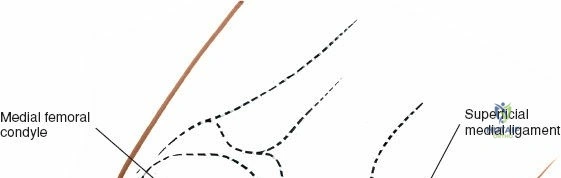

The medial meniscus is a C-shaped, semilunar fibrocartilaginous structure that resides on the medial tibial plateau, acting as an interface between the femoral condyle and the tibial plateau. It is broader posteriorly than anteriorly.

- Body: The central portion, relatively immobile due to its firm attachment to the deep fibers of the medial collateral ligament (MCL) and the joint capsule via the coronary (meniscotibial) ligaments. This firm attachment, in contrast to the more mobile lateral meniscus, contributes to its higher incidence of tears, particularly in conjunction with MCL injuries.

- Landmarks: Palpate the medial joint line, medial epicondyle of the femur, and medial tibial plateau. The saphenous vein and nerve courses superficial and posterior to the medial femoral condyle, requiring careful attention.

Dissection:

- Saphenous Nerve and Vein: Careful dissection is paramount to identify and protect the infrapatellar branch of the saphenous nerve and the greater saphenous vein, which lie within the subcutaneous fat layer. Retract them carefully.

- Joint Capsule: The approach typically involves either a medial parapatellar arthrotomy, splitting the fibers of the vastus medialis obliquus (VMO) longitudinally, or a direct incision of the medial capsule over the joint line, medial to the patellar tendon. For direct access to the medial meniscus, a paramedial capsular incision along the medial border of the patella and extending distally can be made.